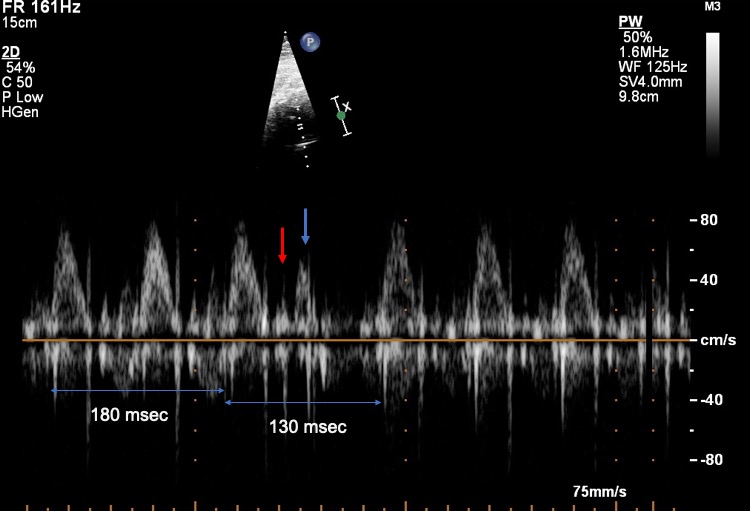

Ventricular ectopic beats more infrequent than atrial ectopic beats and can be identified on fetal echocardiography by the absence of atrial systole before ventricle systole and by the absence of SA nodal reset. The majority of ventricular ectopic beats resolve spontaneously without treatment. Frequent ventricular ectopic beats and the presence of malignant pattern would warrant a heart rate monitoring to ensure that they are infrequent and that there are no episodes of sustained ventricular arrhythmias.